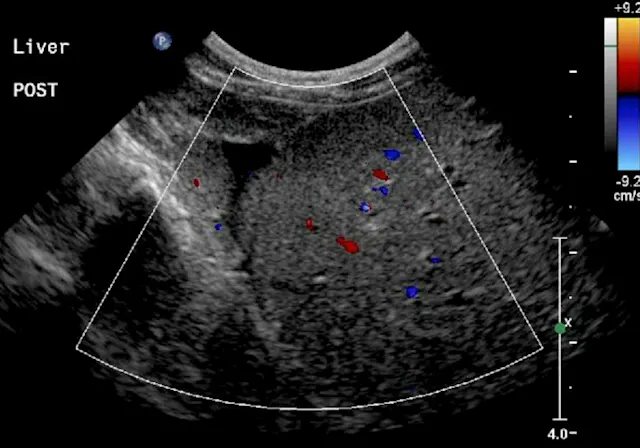

Once the image area is optimized, turn on color flow Doppler to ensure there are no major vessels in the area of interest (Figure 4). The hepatic and portal veins—but not the distribution of the hepatic artery—can be visualized on a standard gray-scale 2-dimensional ultrasound image. Angle to the right and left to ensure that there are no major vessels within the target area. Turn off imaging compounding to ensure accurate needle-tract and needle-tip placement at depth in the liver.

Color Doppler of a potential biopsy area in the liver. On account of the presence of large portal veins (colored in red—flow toward the transducer) and hepatic veins (colored in blue—flow away from the transducer), this area was not chosen for biopsy.